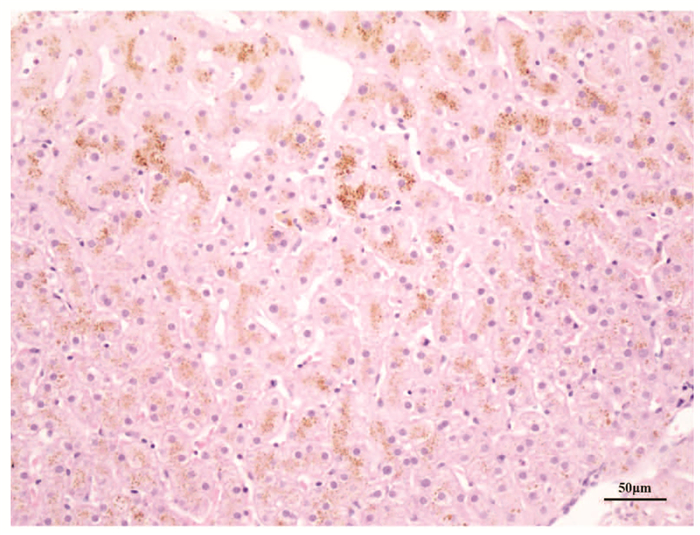

Clinical features of Dubin-Johnson syndrome: An analysis of 10 cases

Figures(2)  / Tables(1)